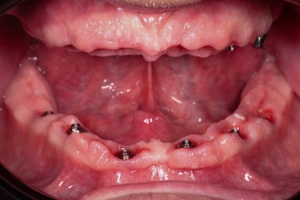

Для комплексного лікування повної адентії (відсутності зубів) використовують метод All-on-4 – вживлення 4 імплантів, на які фіксується незнімна конструкція, яка замінює всю щелепу в деяких випадках використовують ще додатково два імплантати для кращої стабільності подальшої конструкції і тоді така методика називається All-on-6-вживлення 6 імплантатів.

Це технологія яка дозволяє закріпити повній зубний ряд зубів всього на 4 або на 6 імплантатах аледуже часто з вікористанням титанової “шинуючої” фрезированої балки , і чим меньша кількість встановлених імплантатів при тотальнії реабілітації, тім вирогідність шинування імплантатів за рахунок балки вище. тому ця методика має свої плюси та мінуси та свої покази та протипокази.